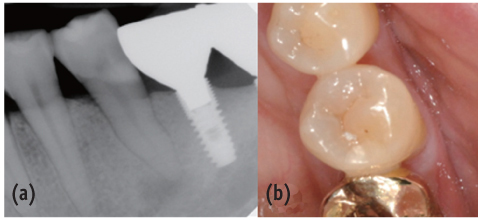

Figure 1

Preoperative periapical view and clinical photograph. (a) Periapical radiolucency on #35; (b) Cervical abrasion.

Figure 1 Preoperative periapical view and clinical photograph. (a) Periapical radiolucency on #35; (b) Cervical abrasion.